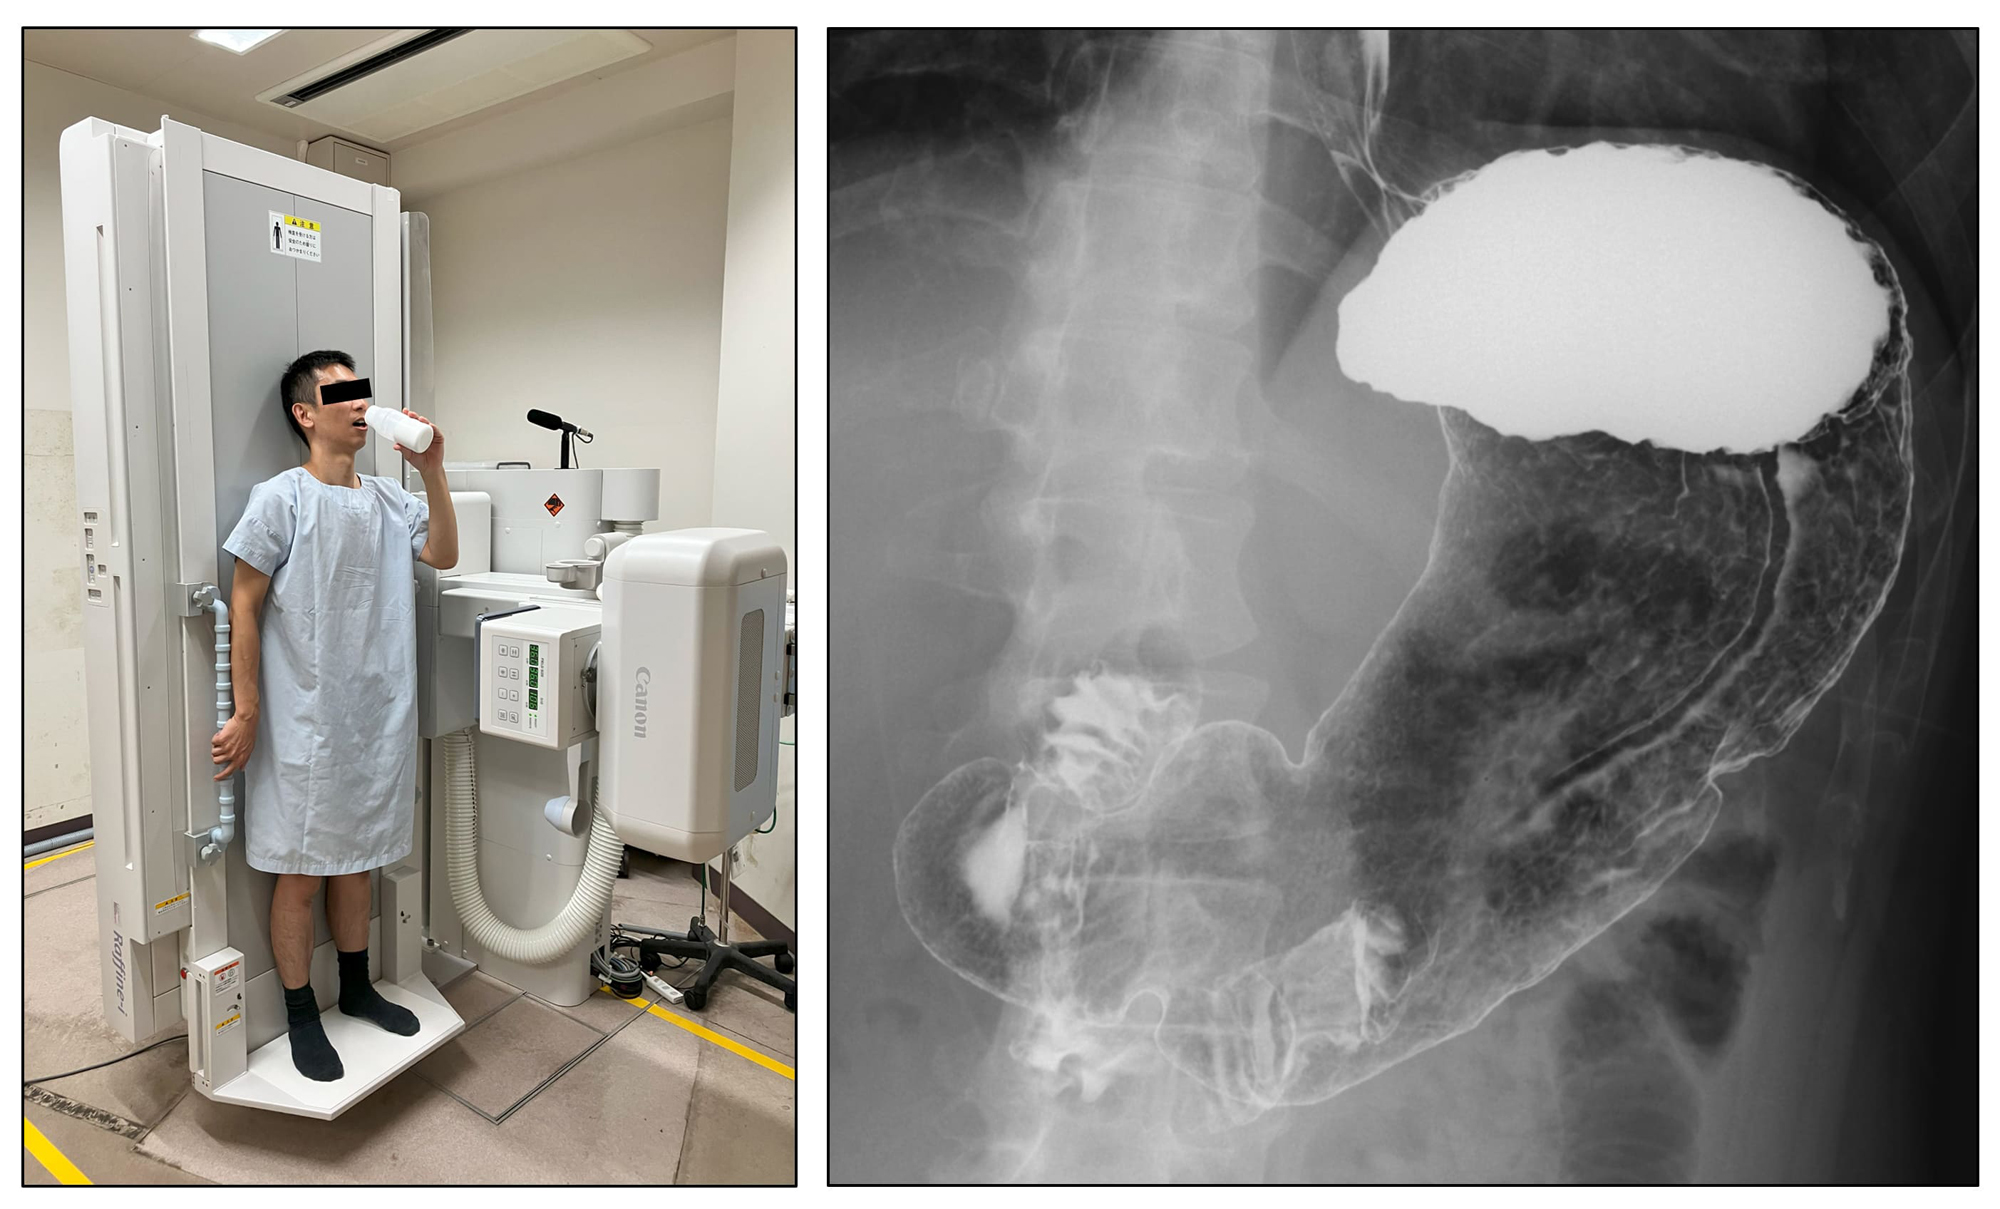

上部消化管造影検査(胃バリウム検査)

- ・バリウムを飲んで、上部消化管(食道、胃、十二指腸)の形状や病変を調べる検査です。

- ・胃がん検診でよく行われます。